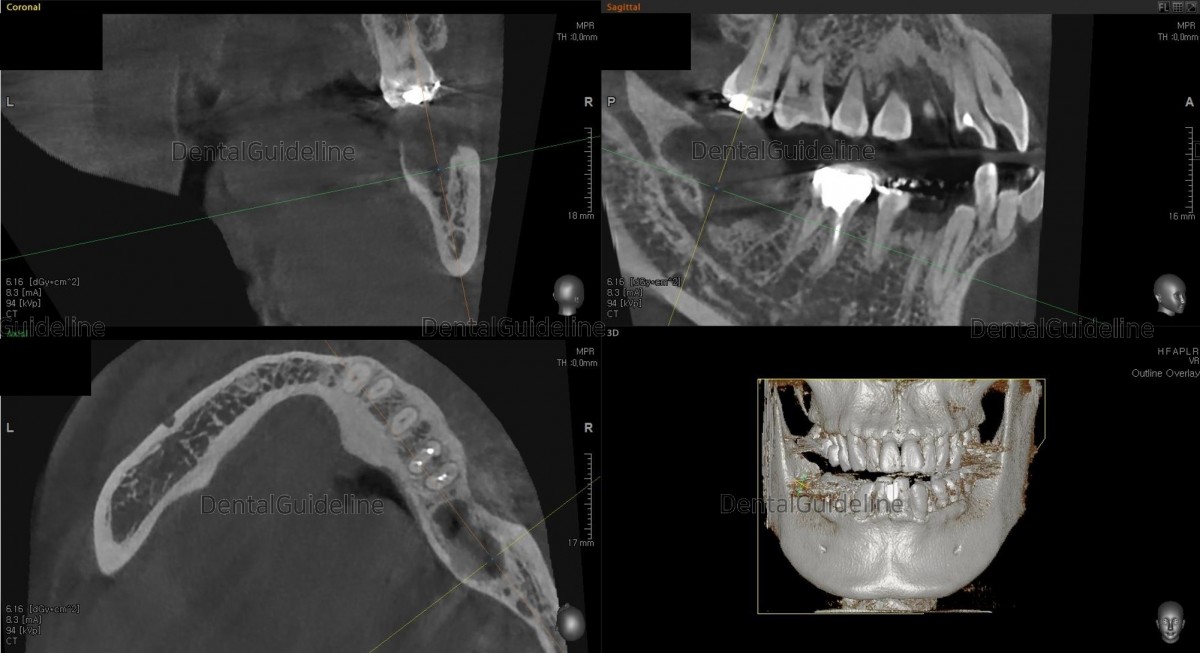

A 46-year-old male patient had mobility, pain, and pus discharge in the 2md molar. In the radiograph, 2nd molar and impacted wisdom tooth extraction are in poor condition. Single implant placement and GBR in the 2nd molar of the mandible after molar and wisdom tooth extraction (staged).

In the radiograph, there is an impacted wisdom tooth lying down, and inflammation is being created at the rear of the second molar.

post-op CBCT

CBCT